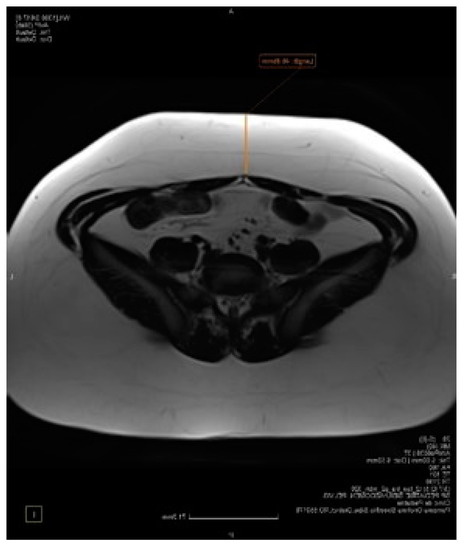

- Shen, W.; Liu, H.; Punyanitya, M.; Chen, J.; Heymsfield, S.B. Pediatric obesity phenotyping by magnetic resonance methods. Curr. Opin. Clin. Nutr. Metab. Care 2005, 8, 595. [Google Scholar]

- Samara, A.; Ventura, E.; Alfadda, A.; Goran, M. Use of MRI and CT for fat imaging in children and youth: What have we learned about obesity, fat distribution and metabolic disease risk? Obes. Rev. 2012, 13, 723–732. [Google Scholar] [CrossRef]

- Eloi, J.C.; Epifanio, M.; de Gonçalves, M.M.; Pellicioli, A.; Vieira, P.F.; Dias, H.B.; Bruscato, N.; Soder, R.B.; Santana, J.C.; Mouzaki, M.; et al. Quantification of Abdominal Fat in Obese and Healthy Adolescents Using 3 Tesla Magnetic Resonance Imaging and Free Software for Image Analysis. PLoS ONE 2017, 12, e0167625. [Google Scholar] [CrossRef]